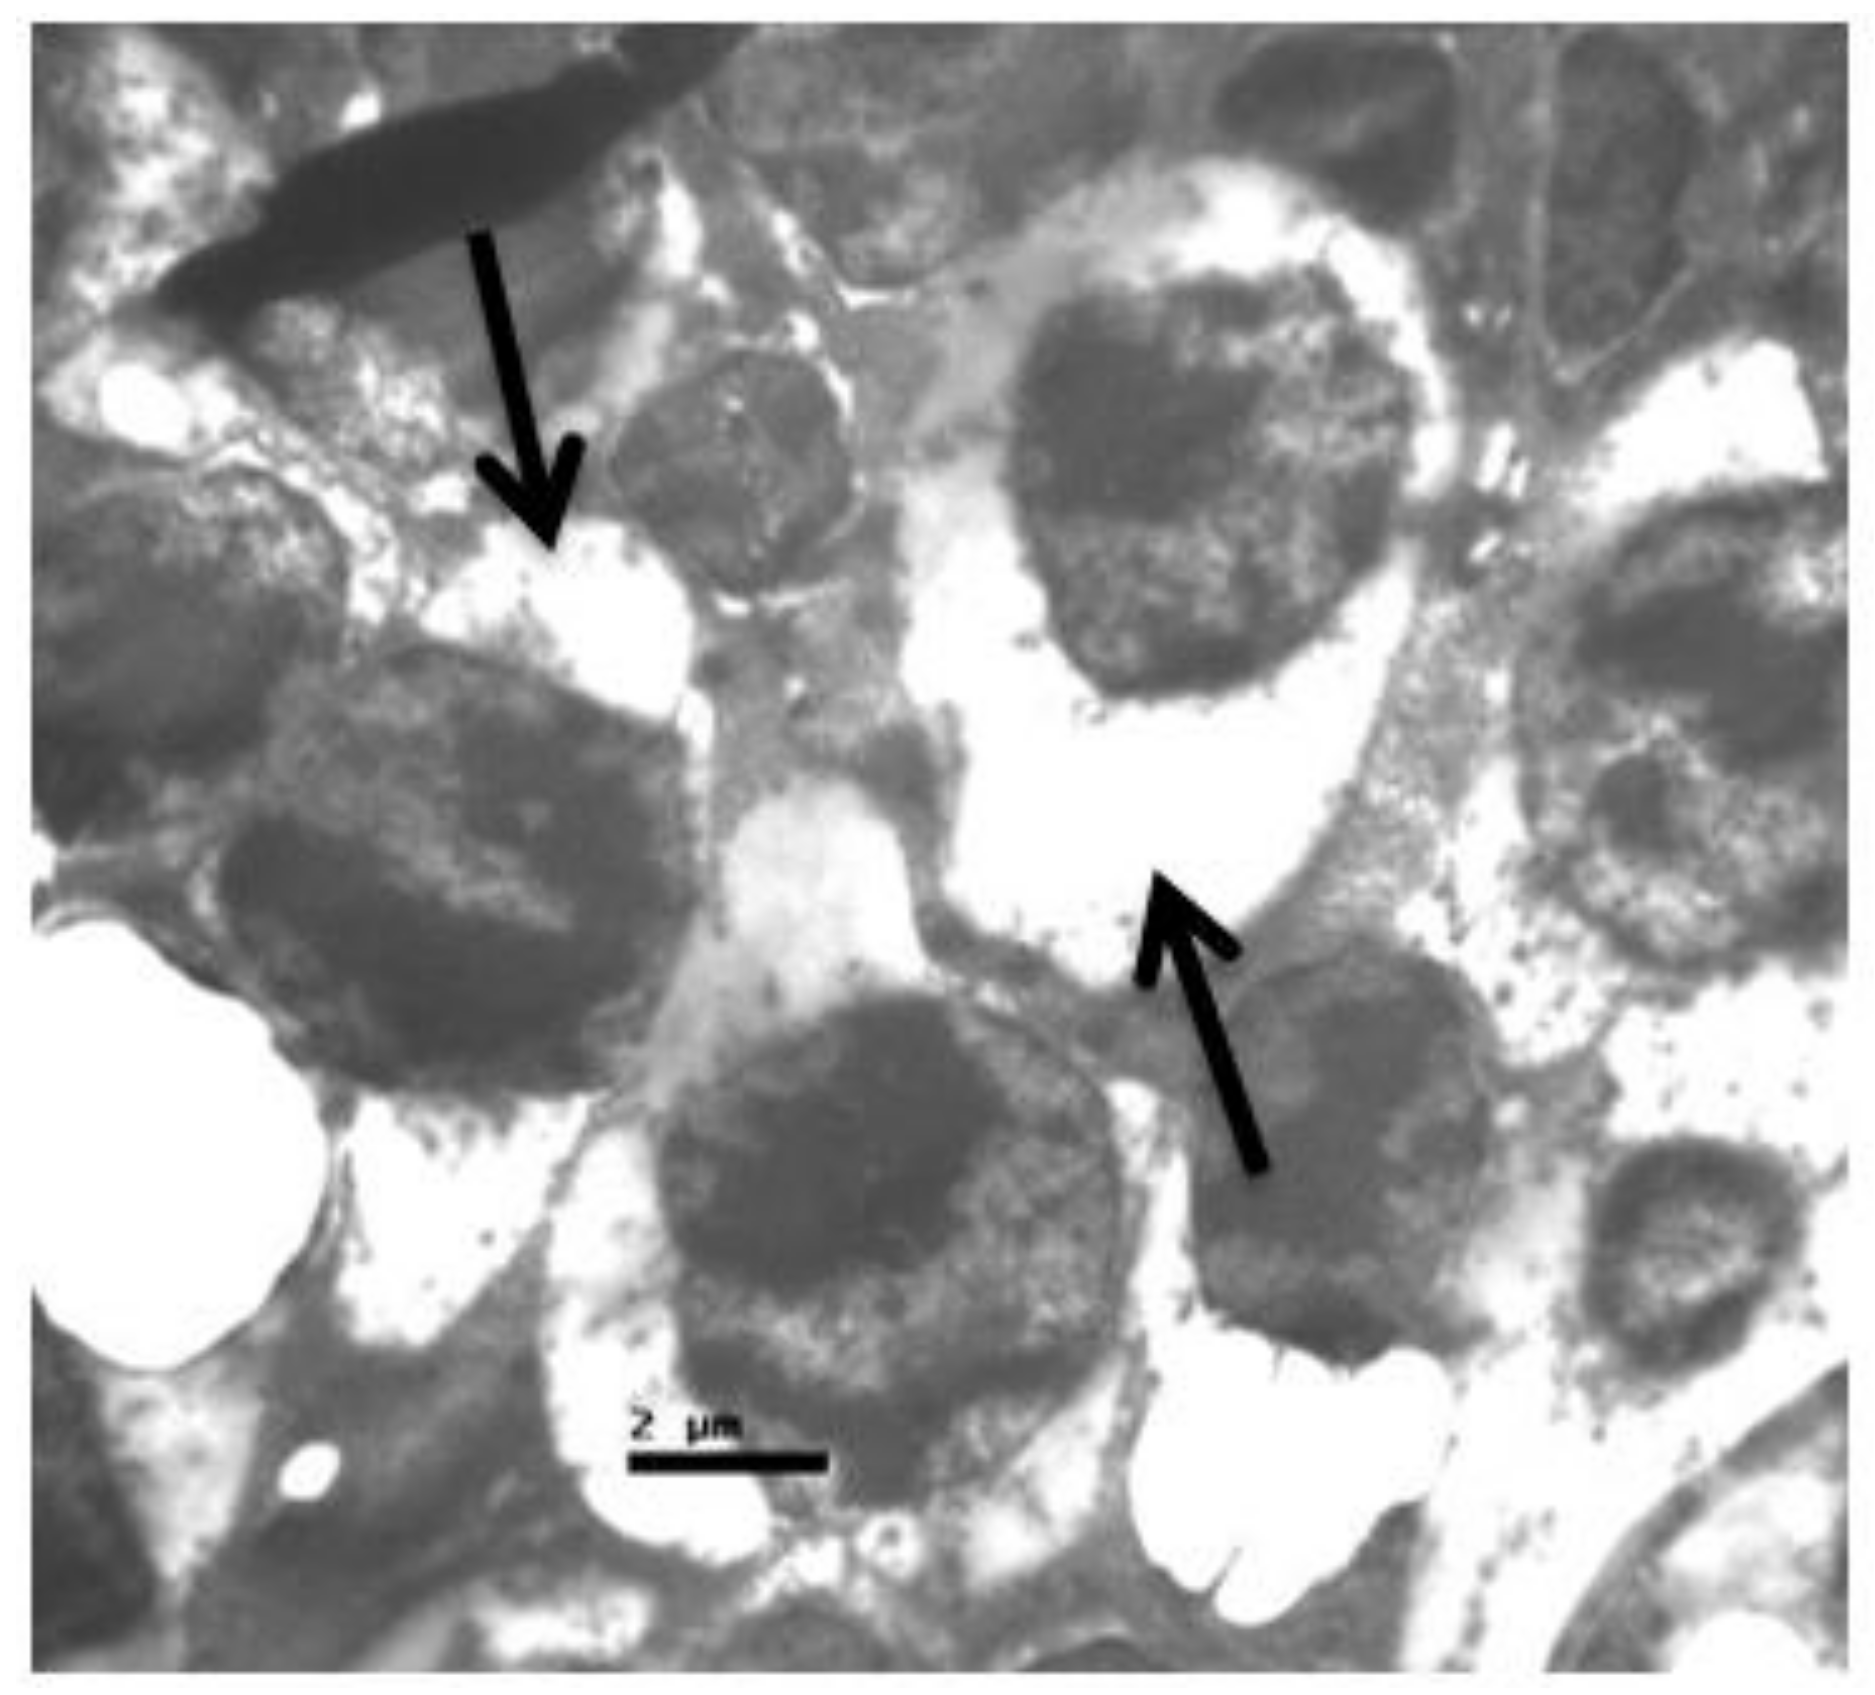

2.2. Group V